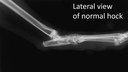

Lateral view of normal hock Lateral view of normal hock